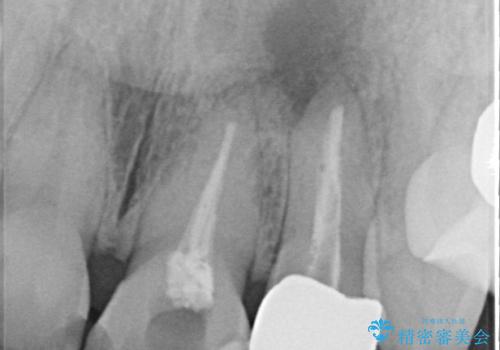

両歯とも根尖部付近を歯肉から触れると痛みを感じており、3次元CTを撮影したところ、前から2番目の歯の根尖部に病変があることが分かりました。

以前歯根端切除術を受けているものの、現在の主流とは異なる術式で行われているため、再度歯根端切除術を行うこととしました。

歯根端切除から2週間を経過した時点で痛みは全くなくなっており、処置から6ヶ月後に撮影したレントゲン写真では炎症で吸収していた骨が回復している様子が確認されました。